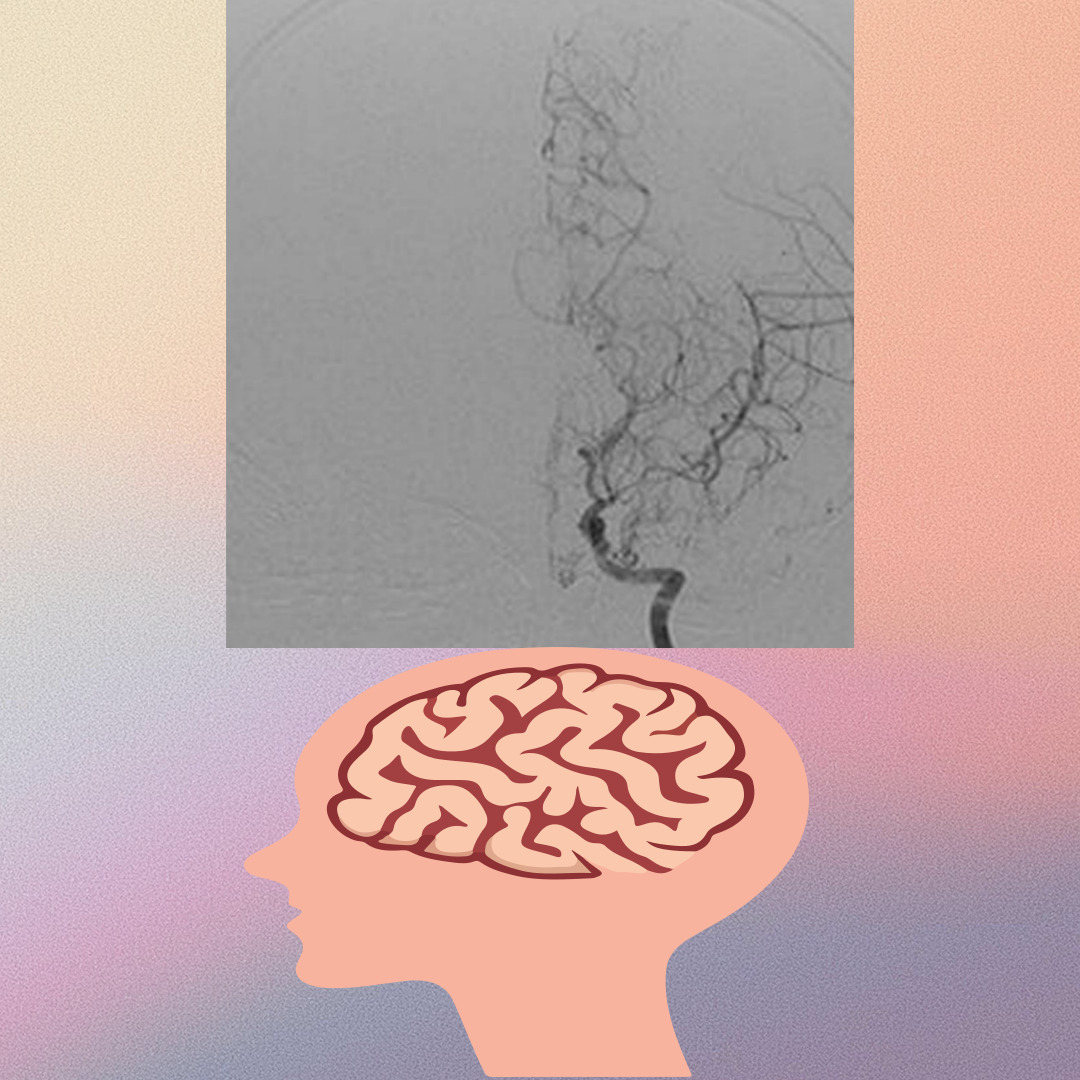

3. 소아 모야모야병 VS 성인 모야모야병 증상 차이

모야모야병 진단은 증상에 의한 의심이 가장 중요하며 일반적으로 소아는 이 병이 일과성 뇌허혈 증상과 뇌경색 등의 경색성 뇌졸중이 나타납니다 반면 성인의 전반이상에서 의식 상실 반신 마비 등의 동반한 출혈성 뇌졸중이 특징적으로 발생합니다.

반면 성인은 갑작스러운 심한 두통으로 시작하는 뇌출혈 때문에 병원을 방문하는 경우가 많으며 또 간질 두통 기억력 저하 때문에 검사를 받다가 발견되기도 하며 언어장애나 시야장애 증상도 발생합니다

희귀 질환인 모야모야병은 확실한 원인이 밝혀지지 않아 모야모야병 자체를 치료할 수 있는 방법이 없습니다 때문에 보존적인 약물 치료와 수술 치료가 시행되고 있으며 수술 치료는 직접 혈관과 혈관을 연결하여 혈류량을 늘리는 직접 혈관 문합술 다른 부분의 혈관이 자라나서 시간이 걸리지만 보조적으로 혈류량을 늘리는 간접 혈관 문합술 그리고 두 수술을 동시에 시행하는 병합 혈관 문합술 세 종류가 있습니다.

소아의 경우 두 수술법 모두 효과적으로 알려져 있으며 성인은 간접 혈관 문합술은 효과자 적어서 주로 직접 혈관 문합술을 시행합니다.